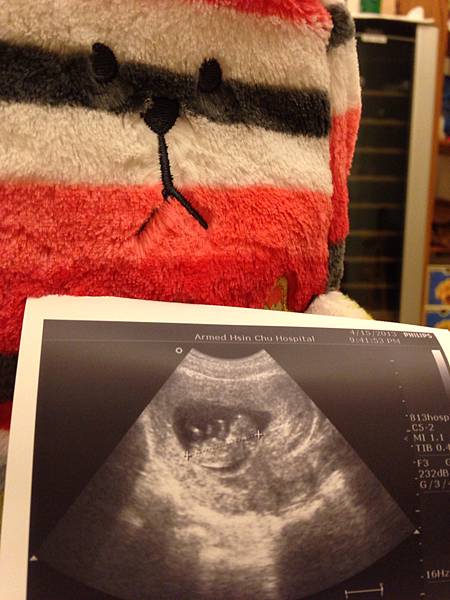

(這是果然有小朋友的樣子了耶)

你現在有4.67cm嚕

心跳164下, 大約是11週3天

可是個有頭有臉的小傢伙, 還看得到你的雙腳呢!

天呐, 真的是個小朋友了耶!